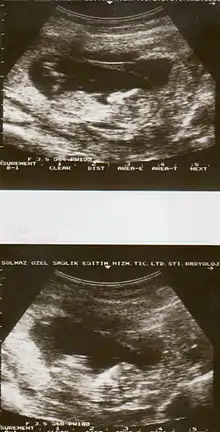

Placental abruption is suspected when a pregnant mother has sudden localized abdominal pain with or without bleeding. The fundus may be monitored because a rising fundus can indicate bleeding. An ultrasound may be used to rule out placenta praevia but is not diagnostic for abruption.[8] The diagnosis is one of exclusion, meaning other possible sources of vaginal bleeding or abdominal pain have to be ruled out in order to diagnose placental abruption.[5] Of note, use of magnetic resonance imaging has been found to be highly sensitive in depicting placental abruption, and may be considered if no ultrasound evidence of placental abruption is present, especially if the diagnosis of placental abruption would change management.[16]